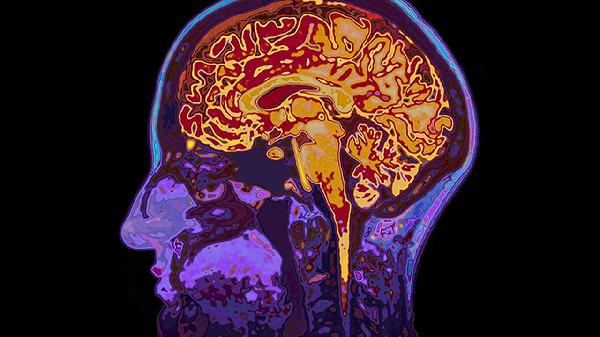

脑血栓片主要用于治疗缺血性脑血管疾病,如脑血栓形成、脑栓塞、短暂性脑缺血发作等。脑血栓片能改善脑部血液循环,帮助恢复脑功能,缓解脑血管疾病引起的一系列症状。

脑血栓片的主要成分为川芎、丹参、赤芍、红花等中药提取物,具有活血化瘀、通经活络的作用。在临床应用中,脑血栓片通常用于缺血性脑卒中恢复期的辅助治疗,对于改善脑部供血不足引起的头晕、头痛、肢体麻木等症状有一定效果。脑血栓片还可用于预防脑血管疾病复发,降低再次发生脑梗死的概率。